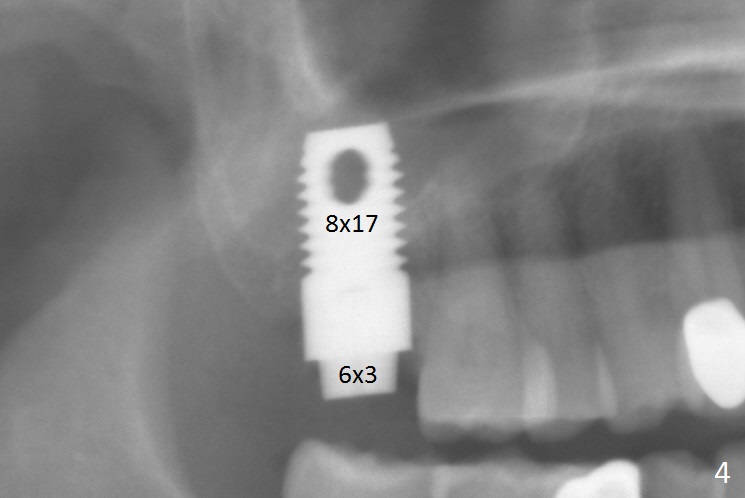

Preop exam shows that the tooth #2 has split into the buccal (Fig.1 B) and palatal (P) halves. When the tooth is extracted (Fig.2), there is a large piece of granulation tissue between these halves. The socket is large with sinus floor having pointed perforation. The latter is enlarged with rounded tapered Tatum osteotomy 2-4 mm, followed by tapered and then rounded taps. A 6.8x14 mm rounded tap has barely enough stability (Fig.3). Following placement of 2 PRF plug and 2 PRF membranes and allograft/Osteogen, a 8x17 mm cylindrical implant is placed with 60 Ncm (implant machine reading), however the implant is unstable (Fig.4). More graft is placed around the implant. With placement of 6x3 mm abutment, an immediate provisional is fabricated to close the socket. There is nasal discharge for a few days postop. PAs taken nearly 6 months postop show no bone loss (Fig.5,6). The definitive crown is cemented with access hole; there is no residual cement (Fig.7 (9 months postop)). The crown is loose 1 month post cementation (last March, Fig.8 with periimplant space (*)). The unipost was not cemented due to gag reflex. He refuses treatment immediately because of the allergy season. When he returns, spray a topical to his throat. Following crown removal, implant is found to have mobility. Panoramic X-ray (Fig.9) and CT (Fig.10,11) show fibrointegration (space) and implant intrusion into the sinus (S) without bone formation. After implant removal, the sinus floor and membrane are found to have been perforated. Osteogen plug is placed, followed by Vanilla/Osteogen (Fig.12 *) and Osteogen plug. It appears that an immediate implant is contraindicated when there is severe infection (Fig.2) with sinus floor perforation. In this case, the bone density at the upper 2nd molar is low (Fig.10 distopalatal view of 3-D image). Bone expansion and condensation is needed for implantation. Progressive loading is also necessity prior to impression.